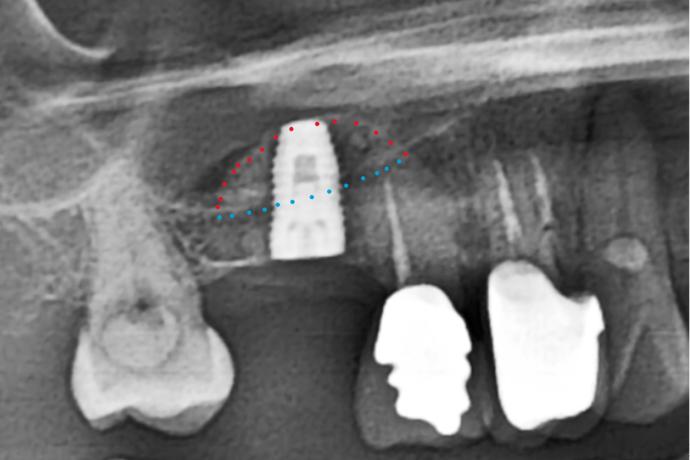

右上第一大臼齒缺牙骨頭高度明顯不足約3mm(如藍色虛線)

術後提昇至10mm且植入植體(如紅色虛線)